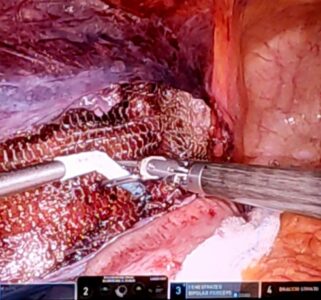

Four intense days of live reports and interventions, where the Glutack + Glubran 2 system was used in various laparoscopic and robotic surgical techniques, from TAPP and TEP to TARUP, from IPOM to TAR and THT.